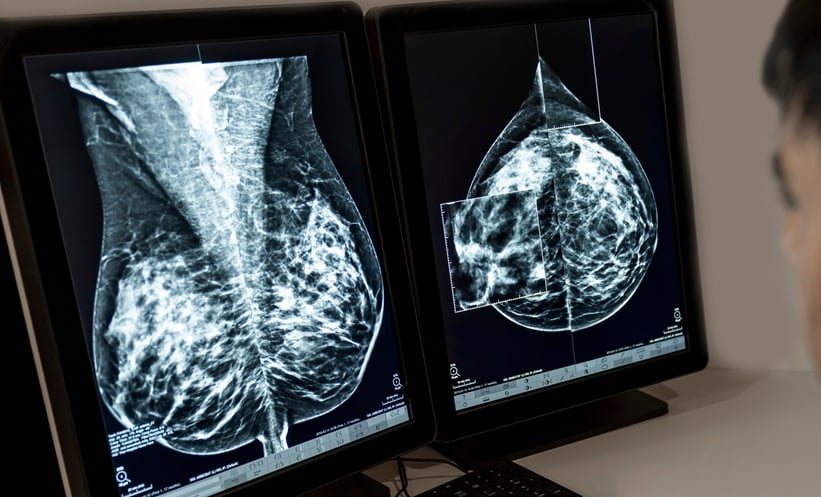

MAMMOGRAPHIC surveillance significantly lowers mortality among survivors of breast cancer and the use of adjunct imaging techniques may enhance early detection, a 2026 systematic review and meta-analysis has found.